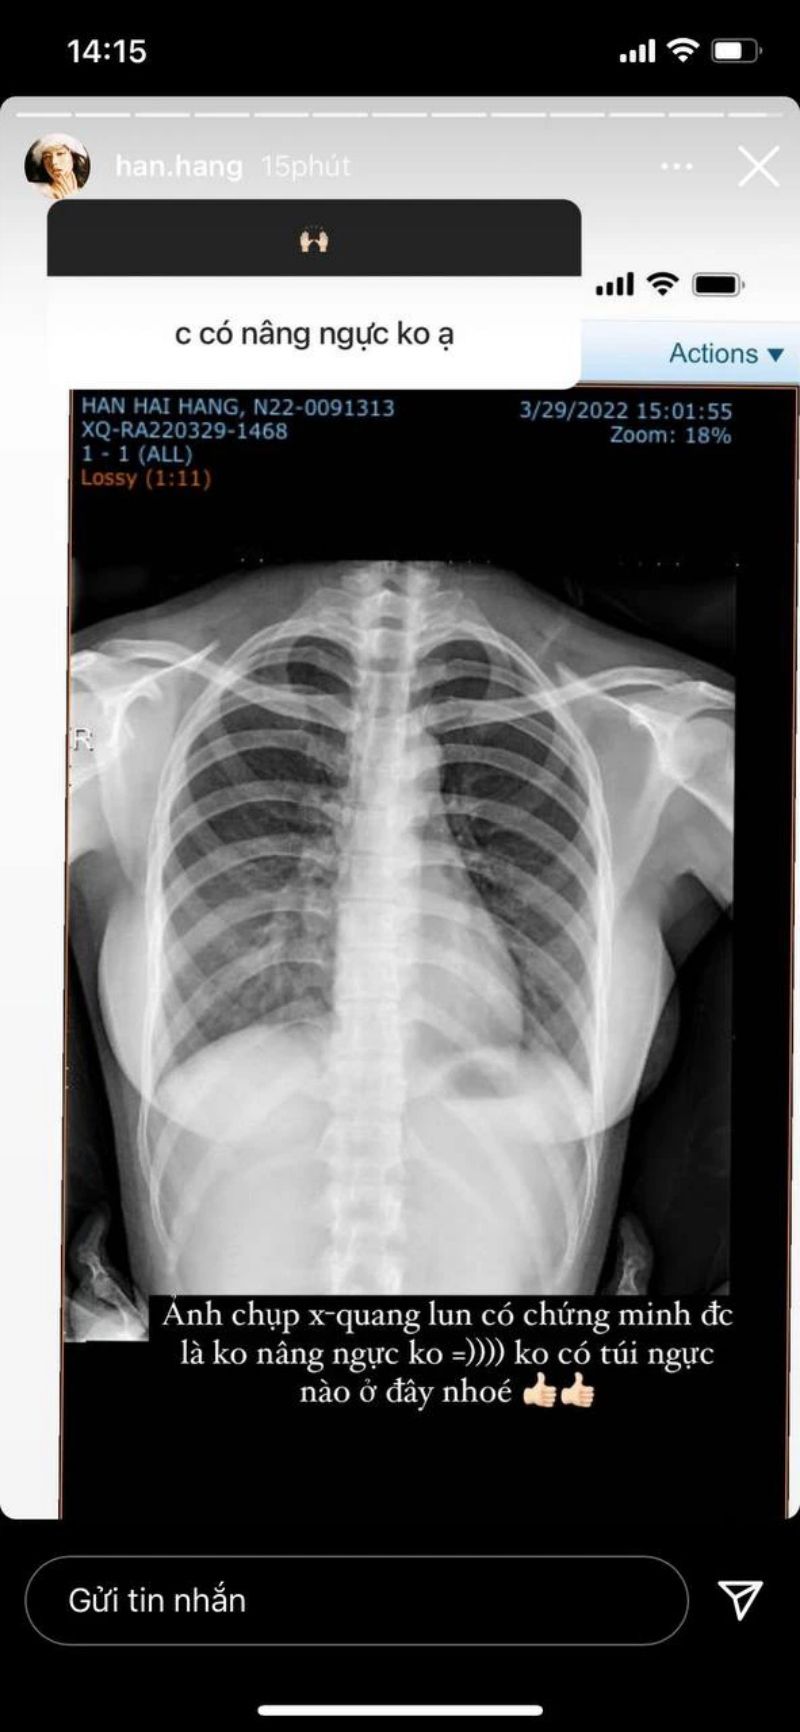

Mới đây, để trả lời cho câu hỏi mà mọi thường thắc mắc là “Hàn Hằng nâng ngực?”, cô đã tung hình chụp X-quang để chứng minh bản thân có vòng 1 đẹp tự nhiên, không hề dao kéo. Đây cũng là cách làm mà nhiều người sử dụng để chứng minh bản thân trong sạch.

Hàn Hằng chia sẻ hình ảnh chụp X-quang minh chứng không có túi ngực nào được sử dụng.